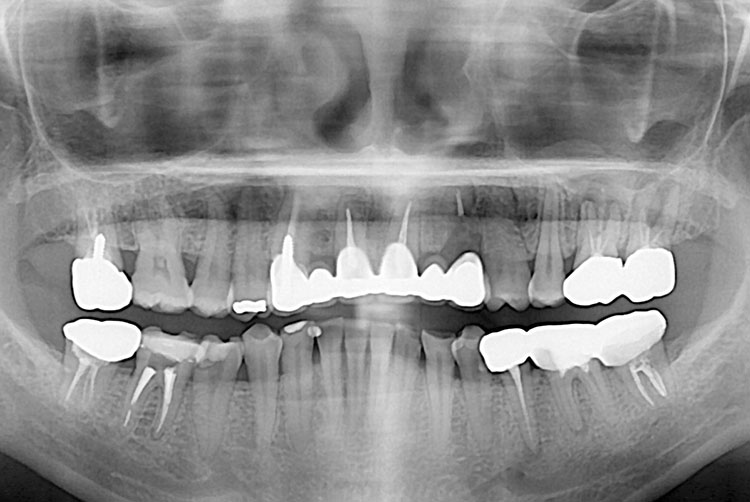

[임플란트] 임플란트

PX20211001_110558_0000_000046C7.jpg

치료후 : 2021-11-01

세종치과는 많은 환자와 다양한 케이스를 바탕으로 항상 편안한 임플란트 수술을 제공하고자 노력하고,

오래동안 튼튼히 쓸 수 있는 임플란트 수술을 가장 큰 목표로 삼고 있습니다